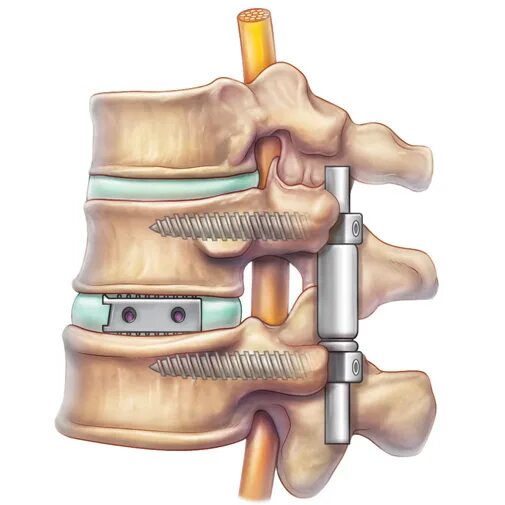

Стабилизирующие операции на позвоночнике